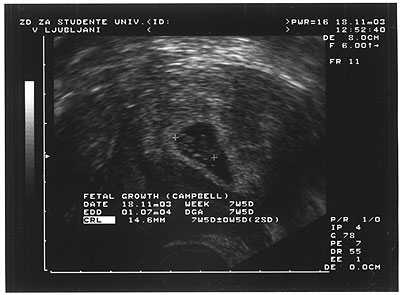

> 5.11.03 - To je pa resnično čisto sveža in zelo privat novica, ampak jo bom vseeno napisal. Nina mi je včeraj poslala sporočilo preko SMS: "Na testu za nosečnost mi je pokazalo, da sem noseča. Zdaj čakam pri ginekologu. LBT Nina." No, torej dragi moji, čas je da pogledamo resnici v oči in si priznamo, da smo že stari. Če bo vse po sreči, bova z Nino drugo poletje dobila svojega potomca (če jih bo več, bomo pa stanovanje prodali in se preselili v veliko hišo!) Uff, nor občutek, sploh pa pozabiš, da sploh kaj drugega obstaja kot ta čudež, ki je velik približno 16mm. Piše se novo poglavje v zgodovini familije Schmidt-Vrabič.

> 18.11.03 - Lahko bi pisal o tem, da delamo stanovanje postopoma, da aktivno koncertiramo s PJ, da zase nimam sploh časa zaradi mnogih projektov, zato bom raje govoril o tem, da smo danes bili na prvem ultrazvočnem slikanju. Hmm, sicer je mala trenutno bolj v obliki ribice, stara okrog osem tednov in če bo vse po sreči bo zadihal(a) nekje poleti sredi julija. Sicer mi pa še ni čisto jasno, da se to res dogaja.